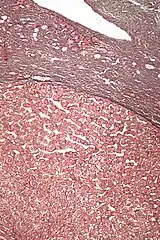

| Micrograph of a hepatic adenoma (bottom of image). H&E stain | |

Hepatic adenomas are, typically, well-circumscribed nodules that consist of sheets of hepatocytes with a bubbly vacuolated cytoplasm. The hepatocytes are on a regular reticulin scaffold and less or equal to three cell thick.

The histologic diagnosis of hepatic adenomas can be aided by reticulin staining. In hepatic adenomas, the reticulin scaffold is preserved and hepatocytes do not form layers of four or more hepatocytes, as is seen in hepatocellular carcinoma.

Cells resemble normal hepatocytes and are traversed by blood vessels but lack portal tracts or central veins.